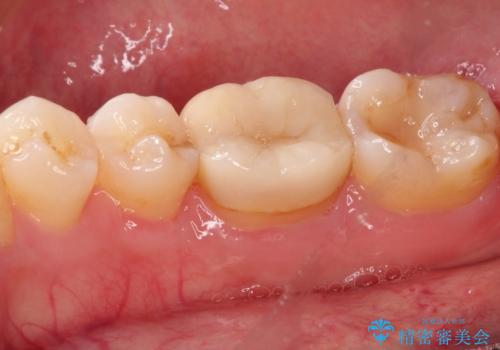

- 以前治療した右下の奥歯の歯の中が虫歯になっている気がするとのことで来院されました。

レントゲン上と視診上では確認できなかったのですが、患者様の希望もあり、一度かぶせ物を外して内部を確認し、オールセラミックを再度装着する計画としました。